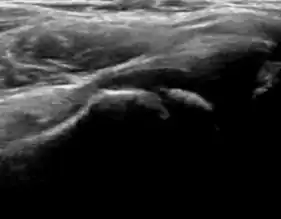

Ultrasound

Ultrasound is the first-choice technique for diagnosis of newborns hip dysplasia. In experienced hands with appropriate technology, ultrasound can also be useful during the first year of life. Some European healthcare systems encourage universal ultrasound screening in neonates between the sixth and eighth weeks. Although it shows higher initial costs caused, it leads to significant reduction in the total number and overall costs of dysplastic hips undergoing operative and nonoperative treatment.[1]

Ultrasound allows categorizing pediatric hips, according to Graf’s criteria, in four main types: normal, immature, and dysplastic (subluxed and dislocated). This classification is based on measurements of the acetabular inclination angle (alpha), cartilage roof angle (beta), and infant age. The femoral head coverage can also be determined by dividing the length of the femoral head covered by the acetabular fossa and the diameter of the femoral head. Its lower normal limits are 47% for boys and 44% for girls (Figure 11).[1]

Figure 11:

-

Useful ultrasound measures in neonatal hip sonography, alpha and beta angles.[1] -

Measurement of femoral head coverage.[1]